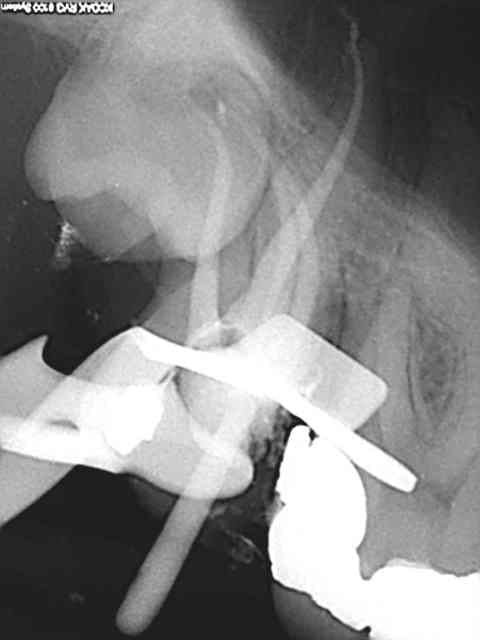

plus d'une heure pour essayer de sauver ces 37 et 38...

mais etait ce vraiment suffisant? cicatrisation possible?